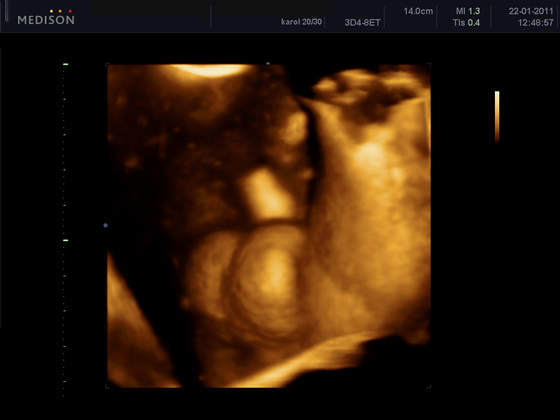

Mój suwak to kłamczuch, dziś mam 36,1, on zawsze pokazuje mi inaczej. Ale jeszcze zeby chociaż z tydzień wytrzymać ... byłam w sobotę u Bielasika, jeszcze raz zobaczył te nerki, stresu nie ma, zmniejszyły się troszkę ale i tak trzeba kontrolować ... mówi, że mały nie wysiusiany i możliwe też dlatego miedniczki powiększone ale jak zobaczył jego klejnoty rodowe to aż się w głos roześmiał. Nie dość ze Miłek ma jaja jak struś, to jego pisiorek miał wzwód, wkleje zdjęcie jak mi się uda.

o udało się!

Same widzicie w czym rzecz